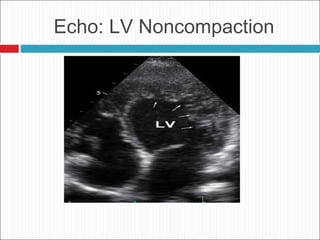

LV Noncompaction

Diagnostic Criteria

 Prominent trabeculations, deep recesses in LV apex

 Thin compact epicardium, thickened endocardium

 associated with multiple genetic variants in the sarcomeric

and other proteins such as tafazzin

Prognosis and Treatment

 Increased risk of CHF, VT/SCD, thrombosis

 Hereditary risk

 Screening of offspring

Echo: LV Noncompaction